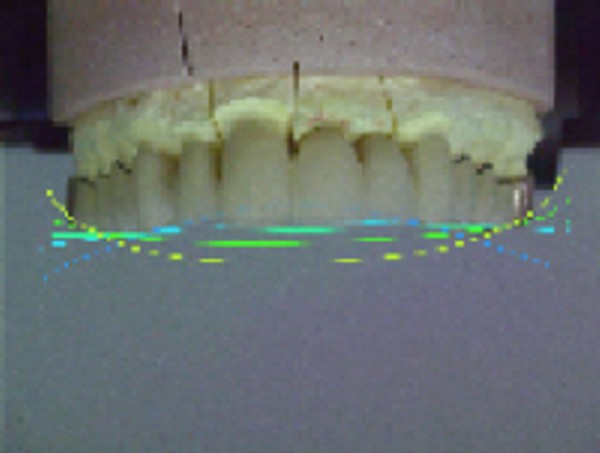

INTRODUCCIÓN El Bruxismo como entidad somática asociada al stress, responde a la mecánica de un Círculo Vicioso Patogénico, que Kawamura describiera hace ya muchos años. FACTOR DESENCADENANTE , que proveen las Interferencias a nivel dentario. En las entregas anteriores se desarrollaron las bases conceptuales de una OCLUSIÓN ORGÁNICA y los efectos de una mayor o menor Desoclusión según la variabilidad de los diferentes Factores Determinantes de la Oclusión. En síntesis; A-La obtención de una Oclusión en Relación Céntrica, nos permite devolver al sistema una elongación muscular fisiológica, sin acortamientos ni estiramientos musculares, sin las consecuentes estimulaciones de los husos neuro musculares, y; una situación estable de la A.T.M. con espacios articulares uniformes. B-El logro de una Guía Anterior que permita desocluir los sectores posteriores durante los movimientos excursivos, nos provée de una segunda y preponderante senda a transitar, que NO estimula por sus contactos excursivos la cincha Pterigo Maseterina, causante de las enormes destrucciones parafuncionales que es frecuente ver en bocas bruxómanas, y la axialización de las fuerzas sobre las piezas posteriores durante el cierre. C-Otorgando como consecuencia, Estabilidad a la tabla premolar-molar, simultaneidad en la recepción de fuerzas durante el cierre(A.T.M. y superficies oclusales). Obtendremos así una Oclusión estable y fisiológica, que no genere el FACTOR DESENCADENANTE del Bruxismo, siempre presente a nivel dentario. INTRODUCTION Bruxism as a somatic entity associated with stress responds to the mechanics of a Pathogenic Vicious Circle, described by Kawamura many years ago. Summarsing: A-Obtaining an oclusion in a Central Relation, allows us to return to the sistem a physiological muscular elongation, without muscular shotthenings or lenghthenings, without the following stimulations of the neuro-muscular huses and a stable situation of the Temporo Mandibular Joint with uniform articular spaces. B-The accomplishment of an Anterior Wide wich may allow disclusive the posterior sectors during the excursives movements, and the axial forces during the mandibular closure. C-Providing as a consecuence, axiality and stability to the posterior sections, responsible of the mandibular closure, through Sttopers, Equalitzers, A, B and C, to obtain a Oclusión Mutuamente Compartida: forces reception during mandibular closure (T.M.J. and Oclusal Surfaces) By this procedure, we should obtain a stable and physiological oclusion, that will not generate the chain link of factors that lead to Bruxism, always present at the dental level. MATERIALES Y MÉTODOS: La funciones articular y muscular, se analizaron mediante Bio Pack, en el pre, en el intra y en el post operatorio. Durante el diagnóstico, tratamiento y remontas, se utilizaron articuladores semi ajustables Wip Mix, totalmente ajustables Artex y arcos faciales correspondientes. El encerado de dianóstico se realizó, mediante la técnica de encerado progresivo de Peter K. Thomas. Los refuerzos a Perno Colado se llevaron a cabo con oro BIODENT YELLOW de ARGEDEN. Los tres juegos de provisionales utilizados, se hicieron con metacrilato termo curado. Las Restauraciones Periféricas Totales, fueron realizadas mediante porcelana CREATION de WILLY GUÉLLER, sobre oro BIODEN YELLOW de ARGEDEN. Los chequeos de los Contactos Interoclusales, se midieron con papeles de articular de 40 y 12 micrones, y mediante el analizador computarizado T-Scan. DESARROLLO Paciente varón de raza blanca, 42 años, complexión robusta y marcada hipertrofia maseterina. Fig.1 Fig.2 Fig.5 Se realiza un análisis pre-operatorio articular y muscular mediante Bio Pack, y oclusal mediante T-Scan, cuyos resultados muestran una evidente hiperactividad muscular en Temporal Anterior y Masetero Derechos, y contactos totalmente anómalos tanto en Oclusión Habitual como en Excéntricas. Fig. 6-7-8-9-10-11 Sensor de ruidos articulares Luego del primer intento de relajación mediante Laminillas de Long (Ref.6),Fig.12, registros y montaje, se observa la aparente presencia de una relación Borde a Borde, que luego se comprobaría que se trataba de una propulsión exagerada de su mandíbula en la búsqueda de contactos efectivos. Fig. 13-14 (Obsérvese el fenómeno de Patterson dado por la exclusiva guía de movimiento de la A.T.M. y la carencia de la Guía Anterior) Se procede a construir un JIG de LUCIA para lograr una desprogramación muscular adecuada, y se le indica permanecer con el colocado durante toda la noche anterior a la consulta, sin contactos dentarios posteriores. Aún en la duda, de que la obtenida sea una posición articular fisiológica, se procede a construir una Placa de Relajación sobre el último montaje obtenido, la que se ajusta cada dos días, y al cabo de tres semanas se procede a un tercer montaje obtenido de la nueva situación posicional. Fig.17-18 Se verifica entonces que estamos en realidad, ante una presunta CLASE II, después de tres métodos diferentes de relajación y transcurridos más de un més de múltiples sesiones para lograr una posición diagnóstica confiable a partir de donde comenzar a trabajar.(O.R.C.) Se adicionan entonces topes (montículos) en las caras oclusales de los primeros molares de la Placa de relajación, transformándola en una Férula Pivotante, de levísima altura, impidiendo el contacto de las demás piezas dentarias a fin de convertir la palanca en una de clase II (fisiológicamente el sistema se mueve según una palanca de clase III), y obtener de esa forma una descompresión de los espacios articulares, ya que si bien la A.T.M. era asintomática, estaba muy claro que la Dimensión Vertical Posterior se presentaba disminuida debido al exagerado desgaste de todos los sectores posteriores, cuya típica forma de «desgaste en olla», se verificaba en el análisis estático de los modelos.( Ref.7) En esa situación se remonta el modelo inferior puesto que el superior no modifica su posición espacial, y se realiza un Encerado de Progresivo Diagnóstico según PKT, previo análisis de los modelos mediante los analizadores de W.McHorris (Ref.8) Fig.18-19-20-21-22-23-24-25-26-27-28-29-30 Fig.18 Fig.22 Fig.23 (Obsérvese, que la Disclusión Propulsiva comienza en los rebordes mesiales del canino, sigue en los rebordes distales del lateral, y finaliza con los rebordes mesiales de los centrales.) Se realizan las endodoncias de toda la boca y se tallan los endodontos para la construcción de Pernos Muñones Colados de oro, los que se realizarán mediante técnica indirecta sobre los modelos :montados según los logros de todos los procedimientos de relajación. Se torna imprescindible la extracción de tres piezas dentarias, para la confección de la Guía Anterior, cuyo alineamiento hubiera sido imposible mediante técnicas reconstructivas ya que la posibilidad ortodóntica no era viable dadas las condiciones de desgaste. Fig.31-32-33-34-35-36-37 (Obsérvese, que desde la configuración de los Pernos Muñones Colados, se determina ya la Alineación Tridimensional que otorgaremos a la Rehabilitación Oral Integral del caso. Se monta entonces el primer juego de Provisionales de acrílico de termo curado, obtenido de la réplica del Encerado de Diagnóstico. Fig.38-39-40-41 (Obsérvese la presencia del ajuste periférico y las disclusiones, tan importantes en las provisorias como en las definitivas ya que del resultado de la etapa de provisionales, dependerá el éxito final.) Se ajustan las Unidades de Oclusión mediante Ajuste Oclusal (según técnica propuesta por la Cátedra de Operatoria Dental II y Prótesis de la Fac. de Odontología, Univ. Bs. As., Prof.Anibal Alonso.) Se deja actuando la nueva situación durante seis meses. Han transcurrido seis meses durante los cuales se instaló un nuevo juego de provisorios con las mismas características del anterior, y clinicamente no se observa hiperactividad muscular, perforaciones de los provisorios, molestias para desmenuzar los alimentos ni síntomas alguno en la A.T.M. NOS ENCONTRAMOS, CON UN SISTEMA EN PAZ A TODOS SUS NIVELES. Se procede entonces a la toma de impresiones definitivas, mediante la técnica de Impresión a Presión Masticatoria, para la confección de las restauraciones permanentes, y los metales se chequean mediante llaves de Duralay, para observar la situación análoga entre laboratorio y clínica.(Corroboración de la Oclusión en Relación Céntrica)Fig.42-43-44 Se prueban los metales y verifica su ajuste periférico. (Obsérvese que también en los metales sub porcelana se siguen las formas de las Preparaciones Funcionales, permitiendo de esta manera un perfecto bizcochado de la porcelana supra metal.) Realizada la Guía Anterior, Determinante Oclusal Primario y Anterior en el laboratorio, se prueban en boca sus características estáticas: Altura Funcional, Ángulo de la Disclusión y Punto de Acoplamiento, como así las dinámicas: Laterotrusión Derecha e Izquierda y Propulsión. En este estado las cosas, tenemos al sistema circunscripto tanto estática, como dinámicamente, por el gobierno de dos comandos, ya en Oclusión en Relación Céntrica, como en las Transtrusiones: Sabemos que todo lo que construyamos (tabla premolar-molar), entre estos dos comandos rectores del movimiento, partirán del mismo punto y volverán a el, transitando el recorrido impuesto por los mismos. Se construyen entonces en el laboratorio, las unidades de oclusión de premolares y molares, siendo las correspondientes a los cuatro últimos molares, con oclusal en oro, como un elemento de detención del cierre más poderoso que la porcelana.47-48-49-50-51 Se prueban en boca la Curva de Wilson, la Curva de Spee, la Alineación Tridimensional, los Espacios Uniformes Disclusivos, la Dirección de los Surcos de T, nT, y P, y los Puntos Interoclusales de Contacto. En laboratorio se retocan entonces los Puntos Interoclusales de contacto, acercando los mismo a la mejor posición ideal lograble, y luego de una nueva prueba en boca, se glacéan las piezas y se instalan en forma provisional durante 24 hs. Verificada la eficacia de las formas (FORMA=FUNCIÓN), se procede a constatar la eficiencia de la dinámica trayectorial y se cementan con cemento de fosfato mediante la técnica de cementado alterno. Fig.54-55-56-57-58-59-60-61-62-63-64-65-66-67-68-69. Fig.54 Fig.55 Curva de Wilson y Alineación Tridimensional en molares y premolares sup. Der. Fig.56 Fig.57 idem inferiores derechos Fig.58 Fig.59 Idem superiores izquierdos CONTACTOS INTEROCLUSALES SUPERIORES CONTACTOS INTEROCLUSALES INFERIORES Transcurrido un mes de instalada la Rehabilitación, se lleva a cabo un nuevo estudio, post operatorio con Bio Pack y Tscan. CONCLUSIONES : I-El paciente realiza una apertura bucal de 45mm sin forzamientos siguiendo una misma línea de apertura sin desvíos. II-Las disclusiones en laterotrusión se llevan a cabo mediante un recorrido lineal sobre los rebordes medios de ambos caninos superiores, creando un fenómeno de Luce con espacios uniformes en ambos lados. III-La disclusión en propulsión se manifiesta comenzando en los rebordes mesiales de ambos caninos, siguiendo por los rebordes distales de laterales y terminando en los rebordes mesiales de ambos centrales, dando lugar a un fenómeno de Christensen con espacios uniformes de ambos lados. IV-Los contactos interoclusales son suficientes, simultáneos y tripódicos logrando la estabilidad en ambos planos del espacio tanto de las piezas individuales como en conjunto, sin contactos deflectivos. V-Realizado un nuevo montaje de la boca terminada, corroboramos como estable la Oclusión en Relación Céntrica. VI-No existen movilidades dentarias y los tejidos periodontales y gingivales se encuentran estabilizados. VII-No existen ruidos articulares. VIII-El resultado post operatorio Bio Pack de la dinámica mandibular, muestra una sustancial mejora de los movimientos en los tres planos del espacio. IX-Electromiográficamente, se observan contracciones musculares dentro de los rangos de normalidad, persistiendo un rango ligeramente elevado en temporal anterior y masetero del lado derecho, presumiblemente debido a la hipertrofia que dicho paciente traía, y mostraba en el estudio pre-operatorio. COMPARACIONES PRE, INTRA Y POST OPERATORIAS Sonografía de la ATM: Tanto en el examen pre como post operatorio no se observaron ruidos de ningún tipo, coincidiendo con la exploración clínica pre auricular e intra auricular. Electromiografía: La electromiografía en reposo, muestra bien a las claras la presencia de músculos hipertónicos durante el estudio pre operatorio, fundamentalmente del grupo Temporal Anterior y Digástricos, estando el Masetero izquierdo ligeramente por encima de su rango normal como así también ambos Esternocleidomastoideos. Durante el estudio post operatorio, se verifica el estado tónico de todos los grupos musculares, persistiendo una ligera hipertonicidad de rango levemente por encima de lo fisiológico, en el Temporal Anterior Derecho y Digástrico Derecho. PRE OPERATORIO POST OPERATORIO Temporal Ant. Der. 4.4 2.8 Temporal Ant. Izq. 6.2 1.1 Masetero Der. 1.2 0.5 Masetero Izq. 1.5 0.8 Est.Cleid.Mast. Der. 1.6 0.3 Est.Cleid.Mast. Izq. 2.1 0.2 Digástrico Der. 1.7 2.9 Digástrico Izq. 1.6 0.7 (La unidad de medida utilizada es el microvoltio ) Dinámica mandibular: Durante el Pre Operatorio, en el Plano Sagital, tanto la Apertura como el Cierre lento, se manifiesta mediante una acentuada tendencia a propulsar la mandibula. Durante el Post Operatorio, la tendencia hacia la derecha de estos dos últimos planos se mantiene, mientras que en Plano Sagital, la propulsión inicial no se produce, asemejándose el movimiento a la primera fase del Bicuspóide de Posselt. El Análisis de la Dinámica realizado durante la Masticación (chicle), nos muestra en el Plano Sagital, la propulsión mencionada durante la apertura y cierre lentos durante el estudio Pre Operatorio, se aproxima a la normalidad durante el Intra Operatorio (2º juego de provisionales), y se vuelve a manifestar propulsivo, en el Post Operatorio. En cuanto al Plano Frontal, durante el Pre Op. , ofrece un Ciclo Masticatorio(recordar la forma de «gota de agua») para el lado izq., con componentes derechos e izquierdos alternos, que se aproximan paulatinamente al Ciclo Masticatorio Normal, durante el Intra y Post Operatorio. El Plano horizontal, confirma las afirmaciones anteriores durante los tres períodos de estudio. ANÁLISIS MEDIANTE TSCAN 1-Bio Pack Bio Research Associates,Inc Distrib.UEDA S.A. 2-Wip Mix-Artex 3-Au:89% / Pt:6% /Elementos complementarios:5% 4-Idem ref.3 5-Tscan TekSkan,Inc Distrib.UEDA S.A. 6-Mc Horris.Cátedra de Operatoria Dental II y Prótesis. 7-Alonso.Cátedra de Operatoria Dental II y prótesis. 8-Mc.Horris. Analizadores de Guía Anterior. BIBLIOGRAFÍA: 1-Esquemas de las dos primeras entregas, tomadas del libro:»Oclusión Orgánica…un camino hacia la Rehabilitación Oral» 2-Oclusión y Diagnóstico en Rehabilitación Oral. 3-Anatomia Odontológica. 4-A contribution to the study of the movementes of the mandible. 5-Celenza F.W, Nadeskin J.F.,Oclusión.Situación actual. 6-D´Amico 7-Dawson P.E. 8-Huffman -Regenos. 9-Hobo S.-Takayama H.A. 10-Lucia V.O 11-Mc Horris. 12-Mc Horris. 13-Posselt U. 14-Stuart C. 15-Vartan Veshnilian AGRADECIMIENTOS: La Rehabilitación Oral, especialidad donde se hace imprescindible el manejo y concurrencia de todas las especialidades dentales en su desarrollo más depurado, no tendría razón de ser, sin la más estrecha colaboración de una técnica para- médica con detalles de excelencia. Sr. Pedro Colomina: muchas gracias. Pedro Colomina. – Titulado especialista en prótesis dental en la escuela Ramon y Cajal de Barcelona 1988

Al cabo de los mismos se realiza una nueva comprobación del estado articular y muscular mediante Bio Pack y un chequeo oclusal mediante T-Scan, donde se observan una evidente mejoría de la musculatura comprometida, de la dinámica mandibular, de la apertura bucal, de los contactos simultáneos de la Oclusión en Relación Céntrica como así de las Excéntricas, y un manifiesto control masticatorio por parte del paciente.

Durante esta última, se obtiene un comienzo en los rebordes mesiales caninos, luego los laterales y por último los centrales, tal como se concibió en el encerado.

Curva Frontal de Wilson

Fig.48

Curva Sagital de Spee